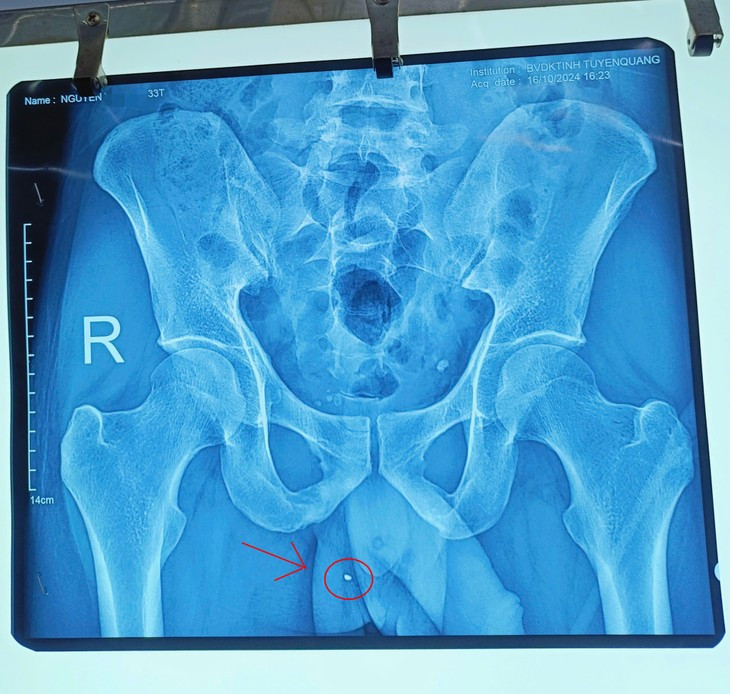

| Hình ảnh dị vật đâm "xuyên táo" tinh hoàn qua phim chụp. Ảnh: BVCC |

Quá trình phẫu thuật, kíp mổ khoa Ngoại Thận – Tiết niệu, Bệnh viện đa khoa tỉnh Tuyên Quang đã phát hiện bệnh nhân có vết thương "xuyên táo" tinh hoàn phải (từ đuôi mào tinh hoàn đến đầu mào tinh hoàn), đang rỉ máu. Kíp mổ đã cẩn thận, tỉ mỉ phẫu thuật lấy ra 01 dị vật kim khí, kích thước khoảng 4mm, sau đó cầm máu kỹ, bảo tồn tinh hoàn và đặt 01 dẫn lưu cho bệnh nhân.